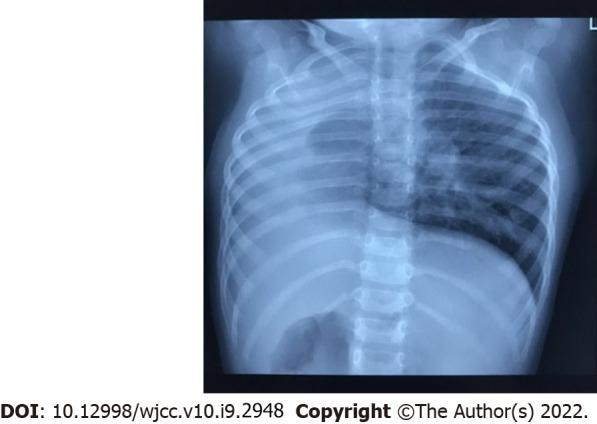

A 2-year-old boy presented to the ear reconstruction department of our hospital complaining of deviation of the face to the right side and auricular anomaly. Physical examination revealed facial asymmetry, preauricular skin tags, and concha-type microtia with stricture of the external auditory canal on the right side. Head magnetic resonance imaging showed bilateral semicircular canal dysplasia and bilateral internal auditory canals stenosis. Audiometric examination showed bilateral severe sensorineural hearing loss. Chest radiography and computed tomography showed dextrocardia and right pulmonary hypoplasia.

This case presented a rare finding and an unusual association of 3 malformations, ipsilateral HFM, pulmonary agenesis, and dextrocardia.